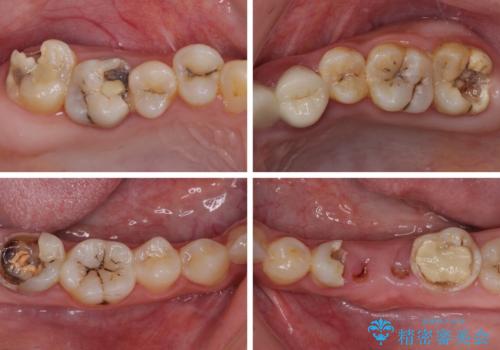

- 歯を削る量が少ないとの触れ込みで最近接着ブリッジを装着したものの、そのブリッジと歯の間に隙間ができているとのことで来院された患者様です。

歯の裏側を一層だけ削り、接着力に頼ったブリッジを装着してはみたものの、案の定咬む力に負けて、接着が剥がれてしまっていました。

歯を削る量は増えますが、より長い期間再治療なく使用していただくことを最優先に考え、フルカバレッジのオールセラミックブリッジにて補綴することとしました。

他にも、奥歯の銀歯の下にもむし歯が多くあり、痛みが生じていたため、根管治療などを行った上で、オールセラミッククラウンにて補綴治療することとしました。